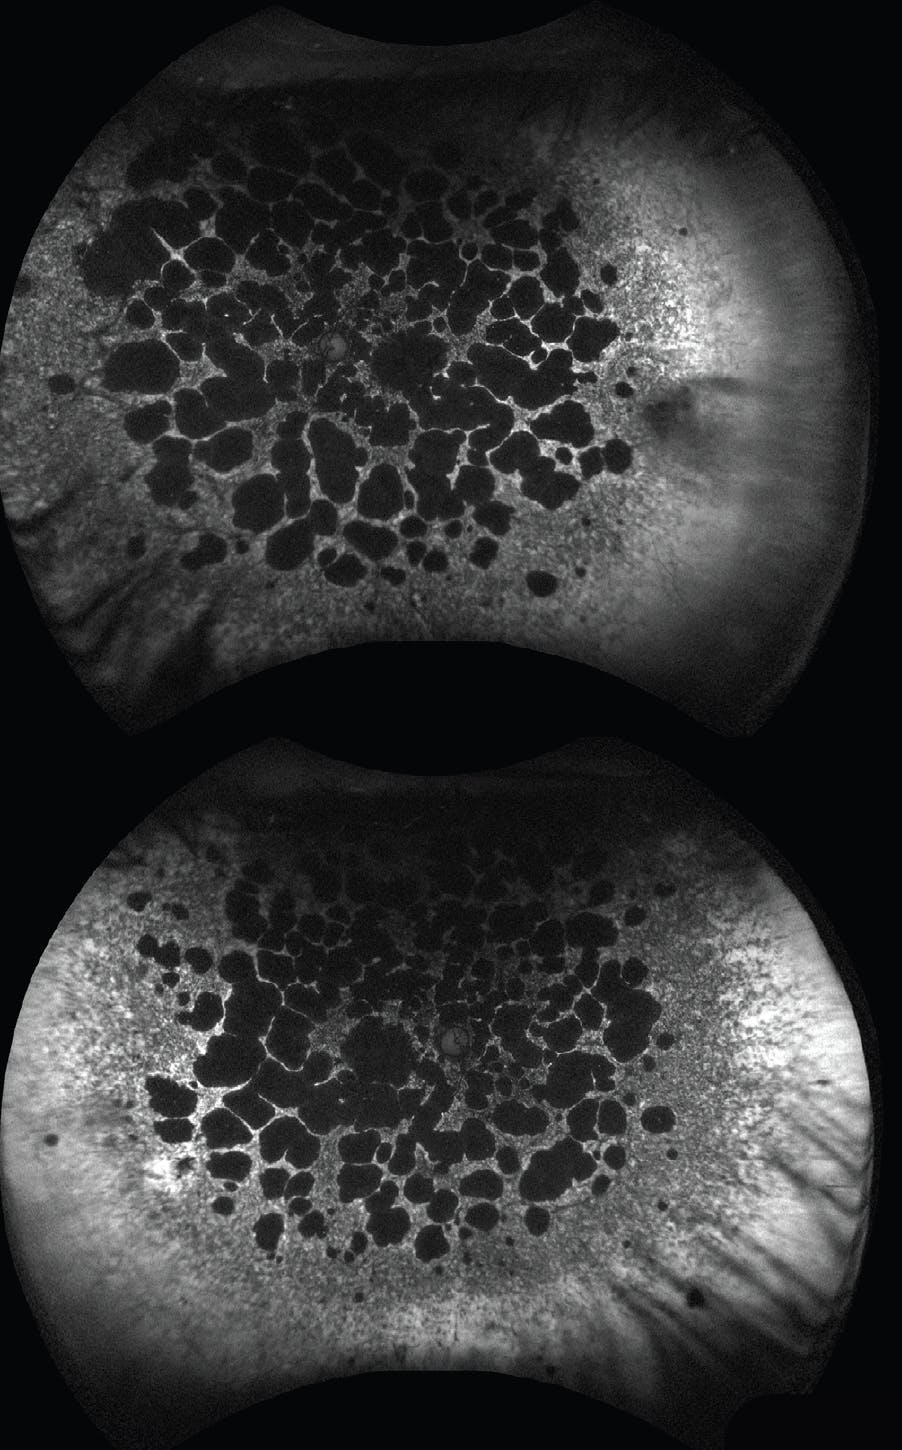

Her BCVA was counting fingers OU. Fundoscopy revealed a bilateral pale optic disc, diffuse retinal pigment epithelial degeneration, and pigment clumping in each eye (Figure 1). Fundus autofluorescence showed symmetric demarcated areas of atrophy, mostly nonconfluent, throughout the posterior pole without peripapillary sparing (Figure 2).